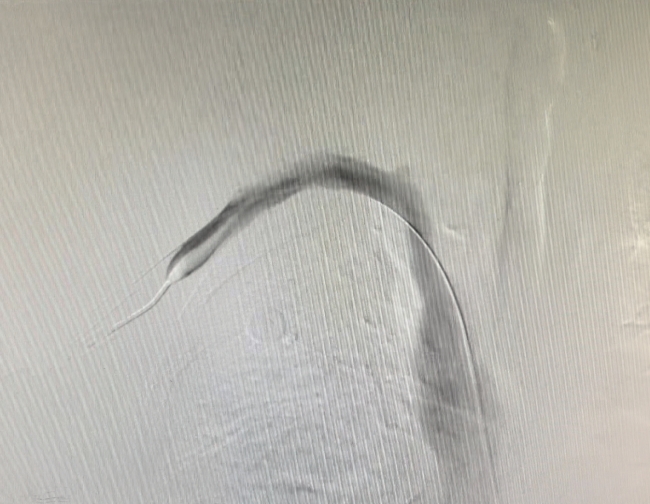

术中造影显示右侧头臂静脉闭塞,侧支血管开放

在医务人员的精心安排下,欧大叔被顺利送入手术室。术中,手术团队经右上肢动静脉内瘘血管穿刺,置入导管鞘,经造影导管造影再次证实右侧头臂静脉闭塞,利用导丝、导管配合反复多次均无法通过患者头臂静脉闭塞病变,考虑为陈旧性病变,随后改行股静脉穿刺置鞘,利用子母导管技术成功通过了闭塞病变,经球囊扩张后,患者的右侧头臂静脉开通,复查造影显示中心静脉通畅,困扰患者多时的难题终于解决了。